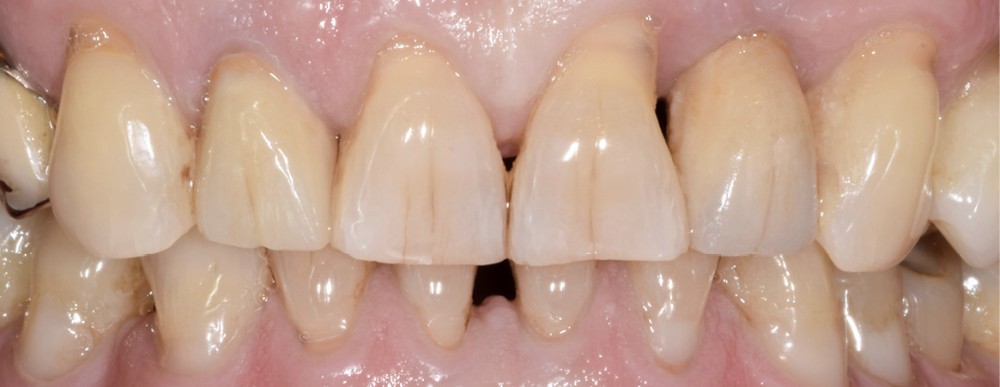

Au vu des conditions initiales, il nous apparaît impossible de restaurer une esthétique satisfaisante, notamment au niveau de l’alignement des collets, sans une chirurgie muco-gingivale associée à une réhabilitation des dents antérieures par facettes. En effet, la perte de la 22, associée à une forme triangulaire des dents, a provoqué un non-alignement des collets ainsi que la présence de trous noirs entre les dents 21-22 et 22-23. Cependant, les contraintes exprimées par le patient contre-indiquaient ce traitement.